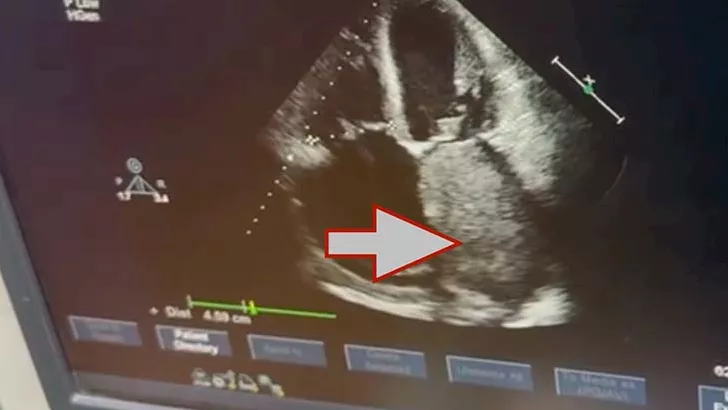

نجح فريق جراحة القلب والصدر بكلية الطب جامعة القاهرة في إجراء جراحة قلب معقدة لاستئصال ورم ضخم من داخل الأذين الأيسر لقلب مريض يبلغ من العمر 72 عامًا، بلغ حجمه نحو 10 × 8 سنتيمترات، وهو حجم نادر لمثل هذه الأورام القلبية.

وأوضح الفريق الطبي أن الورم من نوع Cardiac Myxoma، وهو من الأورام القلبية النادرة التي تنشأ داخل حجرات القلب، وقد تسبب في انسداد شديد بفتحة الصمام الميترالي أثناء تدفق الدم، ما أدى إلى ارتفاع ملحوظ في ضغط الشريان الرئوي، نتج عنه ارتجاع شديد بالصمام الثلاثي الشرفات، إضافة إلى تضخم بالأذين الأيسر وحدوث ذبذبة أذينية.

وخلال الجراحة التي استغرقت نحو أربع ساعات، تمكن الفريق الجراحي من استئصال الورم بالكامل مع قاعدته من الحاجز الأذيني، ثم إعادة ترميم الحاجز الأذيني باستخدام الغشاء التاموري، كما تم إجراء إصلاح جراحي للصمام الثلاثي الشرفات لعلاج الارتجاع الناتج عن ارتفاع ضغط الشريان الرئوي.

ويُعد حجم الورم من الحالات النادرة نسبيًا، إذ يُصنف ضمن الأحجام الكبيرة للأورام التي يتم استئصالها من داخل القلب، ما يعكس مستوى الدقة والخبرة التي تتمتع بها الفرق الجراحية داخل مستشفيات قصر العيني.